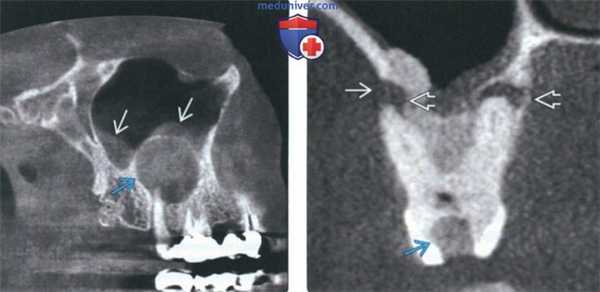

(Слева) На аксиальной КЛКТ определяется периапикальный рарефицирующий остеит вокруг верхушечной трети корня клыка нижней челюсти справа. Рарефицирующий остеит выглядит как неровный гиподенсный ободок вокруг вершины корня зуб.

(Справа) На аксиальной КЛКТ в области моляров верхней челюсти справа определяется рарефицирующий остеит у вершин всех трех корней первою моляра. Видны дефекты лицевой и язычной кортикальных пластинок альвеолярной кости. Определяется также утолщение слизистой оболочки верхнечелюстной пазухи. (Слева) На панорамной реформатированной КЛКТ определяется рарефицирующий остеит у вершины второго премоляра верхней челюсти слева и мезиального щечного корня первою моляра. Все корни были ранее пролечены, но на данный момент требуется повторное лечение или апикоэктомия. Обратите внимание на большую муцинозную псевдокисту в пазухе.

(Справа) На профильном срезе (КЛКТ) определяется расширение периапикального пространства ПДС моляра верхней челюсти. Обратите внимание на снижение плотности кортикальной пластинки дна верхнечелюстной пазухи с воспалительными изменениями в ней, которые могут иметь одонтогенную природу.